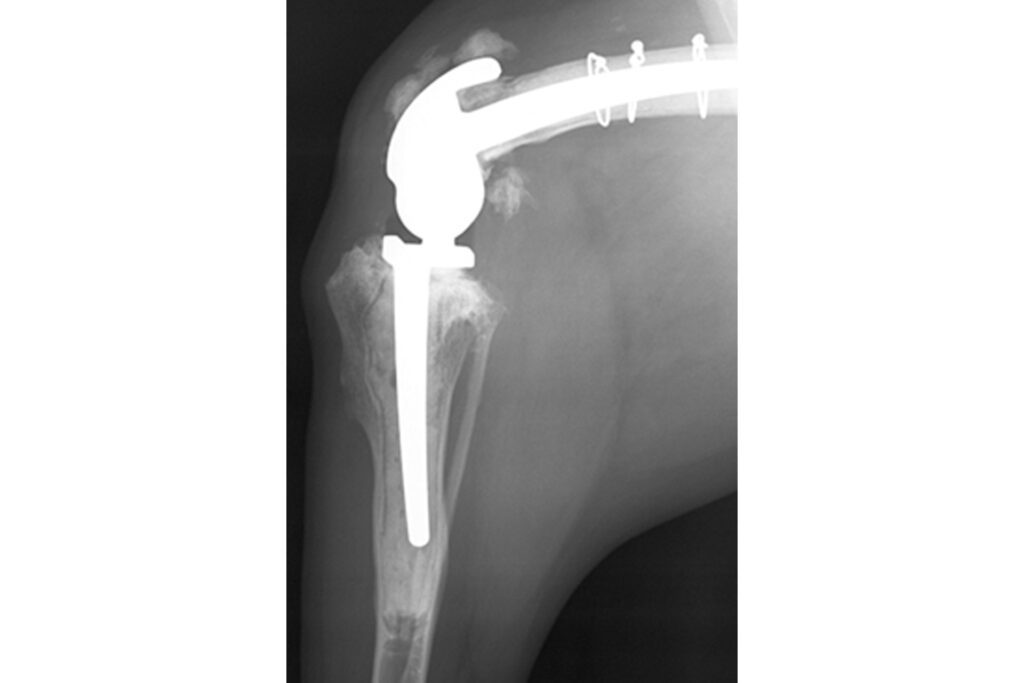

Lucy | Custom hinged total knee replacement

Lucy is a 10-year-old golden retriever who was referred with significant pain and lameness affecting her left hind limb, attributed to considerable arthrosis of the knee. A CT scan revealed collapse of the medial compartment (one half of the knee) with bone-on-bone wear and complete erosion of the caudo-medial tibial plateau (parts of the tibia articular surface). In Lucy’s case, the cruciate and collateral ligaments were disrupted. Therefore, a custom rotating-hinge total knee replacement was designed and manufactured for her. The two components had one metal stem each that were anchored into the femur and tibia using cement, while hydroxyapatite cover on metal surfaces that had direct contact with bone helped with bone on-growth.

Six months postoperatively, Lucy’s lameness has completely resolved and she enjoys unrestricted activity.